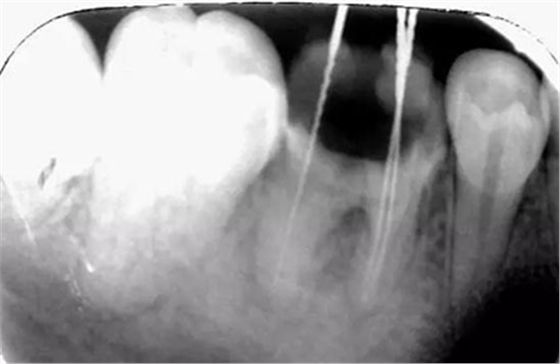

初尖銼,根測儀測量長度后拍照

初尖銼X光片:現(xiàn)在根測儀的準確性的卻非常之高。